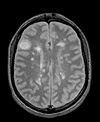

this is the inter-subject moving image, but also the reference for exam 2 this is the inter-subject moving image, but also the reference for exam 2 lleft this is the moving image.

exam 2: PD exam 2: T2 exam 2: T1-Gd

This scenario occurs in many forms whenever we wish to assess change in a series of multi-contrast MRI. The follow-up scan(s) are to be aligned with the baseline, but also the different series within each exam need to be co-registered, since the subject may have moved between acquisitions. Hence we have a set of nested registrations. This particular exam features a dual echo scan (PD/T2), where the two structural scans are aligned by default. The post-contrast T1-GdDTPA scan however is not necessarily aligned with the dual echo. Also the post-contrast scan is taken with a clipped field of view (FOV) and a lower axial resolution, with 4mm slices and a 1mm gap (which we treat here as a de facto 5mm slice). read more about this dataset here

• moving: PD.2 follow-up exam 0.9375 x 0.9375 x 3 mm voxel size, axial acquisition.

• moving: T2.2 follow-up exam 0.9375 x 0.9375 x 3 mm voxel size, axial acquisition. -> same orientation as PD2, will have same transform applied

• moving:T1.2-GdDTPA follow-up exam0.9375 x 0.9375 x 5 mm voxel size, axial acquisition. -> undergoes 2 transforms: first to PD.2, then to PD.1